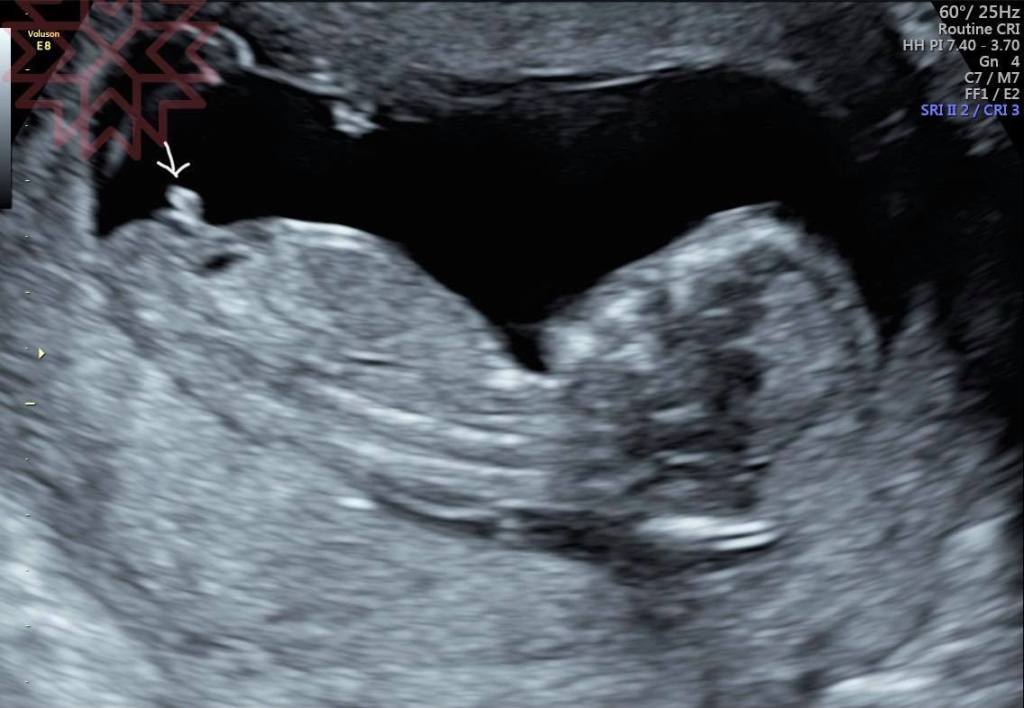

所以真的要看就像我最後兩張圖我們可以用2D的超音波縱切面來去稍微做判斷

請看第一張圖

就是看角度

男寶寶角度比較大女寶寶角度比較小

最後兩張圖就給你猜猜哪個是男寶寶那個是女寶寶好了

正確率大概比用猜的50 %上升到八成左右有人會說到九成其實聽聽參考就好啦

我也看過很多明明幾分鐘前覺得像女寶寶結果過了半小時角度就變不一樣的